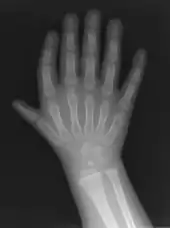

Triphalangeal thumb

Triphalangeal thumb (TPT) is a congenital malformation where the thumb has three phalanges instead of two. The extra phalangeal bone can vary in size from that of a small pebble to a size comparable to the phalanges in non-thumb digits. The true incidence of the condition is unknown, but is estimated at 1:25,000 live births.[1] In about two-thirds of the patients with triphalangeal thumbs, there is a hereditary component.[2] Besides the three phalanges, there can also be other malformations. It was first described by Columbi in 1559.[3]

The triphalangeal thumb has a different appearance than normal thumbs. The appearance can differ widely; the thumb can be a longer thumb, it can be deviated in the radio-ulnar plane (clinodactyly), or thumb strength can be diminished. In the case of a five-fingered hand it has a finger-like appearance, with the position in the plane of the four fingers, thenar muscle deficiency, and additional length. There is often a combination with radial polydactyly.